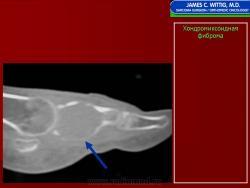

Хондромиксоидная фиброма

Хондромиксоидная фиброма

Хондромиксоидная фиброма

Хондромиксоидная фиброма

Хондромиксоидная фиброма

Хондромиксоидная фиброма

Рентгенологическая картина. Хондромиксоидная фиброма длинных трубчатых костей в типичных случаях представлена метафизарным или метадиафизарным, эксцентричным, четко очерченным, овальным очагом разряжения костной ткани с истон чением и вздутием коркового слоя с одной стороны.